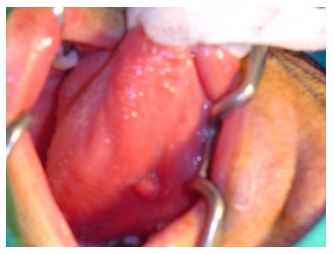

A thirty-year-old male without any previous medical history came to the accident and emergency department, at the General Hospital of the main city of this area. He complained of mouth pain. There was a large tuna fish bone on the mid right dorsal border of the tongue, which was removed. A few days later, he represented with a painful swelling of the tongue. A glossal abscess was aspirated with a large bore needle. An oral wide spectrum antibiotic and a non-steroidal anti inflammatory drug were prescribed. Two weeks later he returned with an increased tongue swelling without compromising the airway which showed a deep lesion in the lingual muscle (Figure 1&2) to the left of the midline Under general anaesthesia a wide incision of the lesion on the ventral tongue the direction of Wharton’s and further dissection of the former abscess opening. A silicone drain was left in place and the incision closed by three stitches. The patient improved a few hours after, and the episode resolved completely without any further complications (Figure 3&4).

Figure 1

Figure 1: Nuclear Magnetic resonance of the lesion in the right sided tongue.